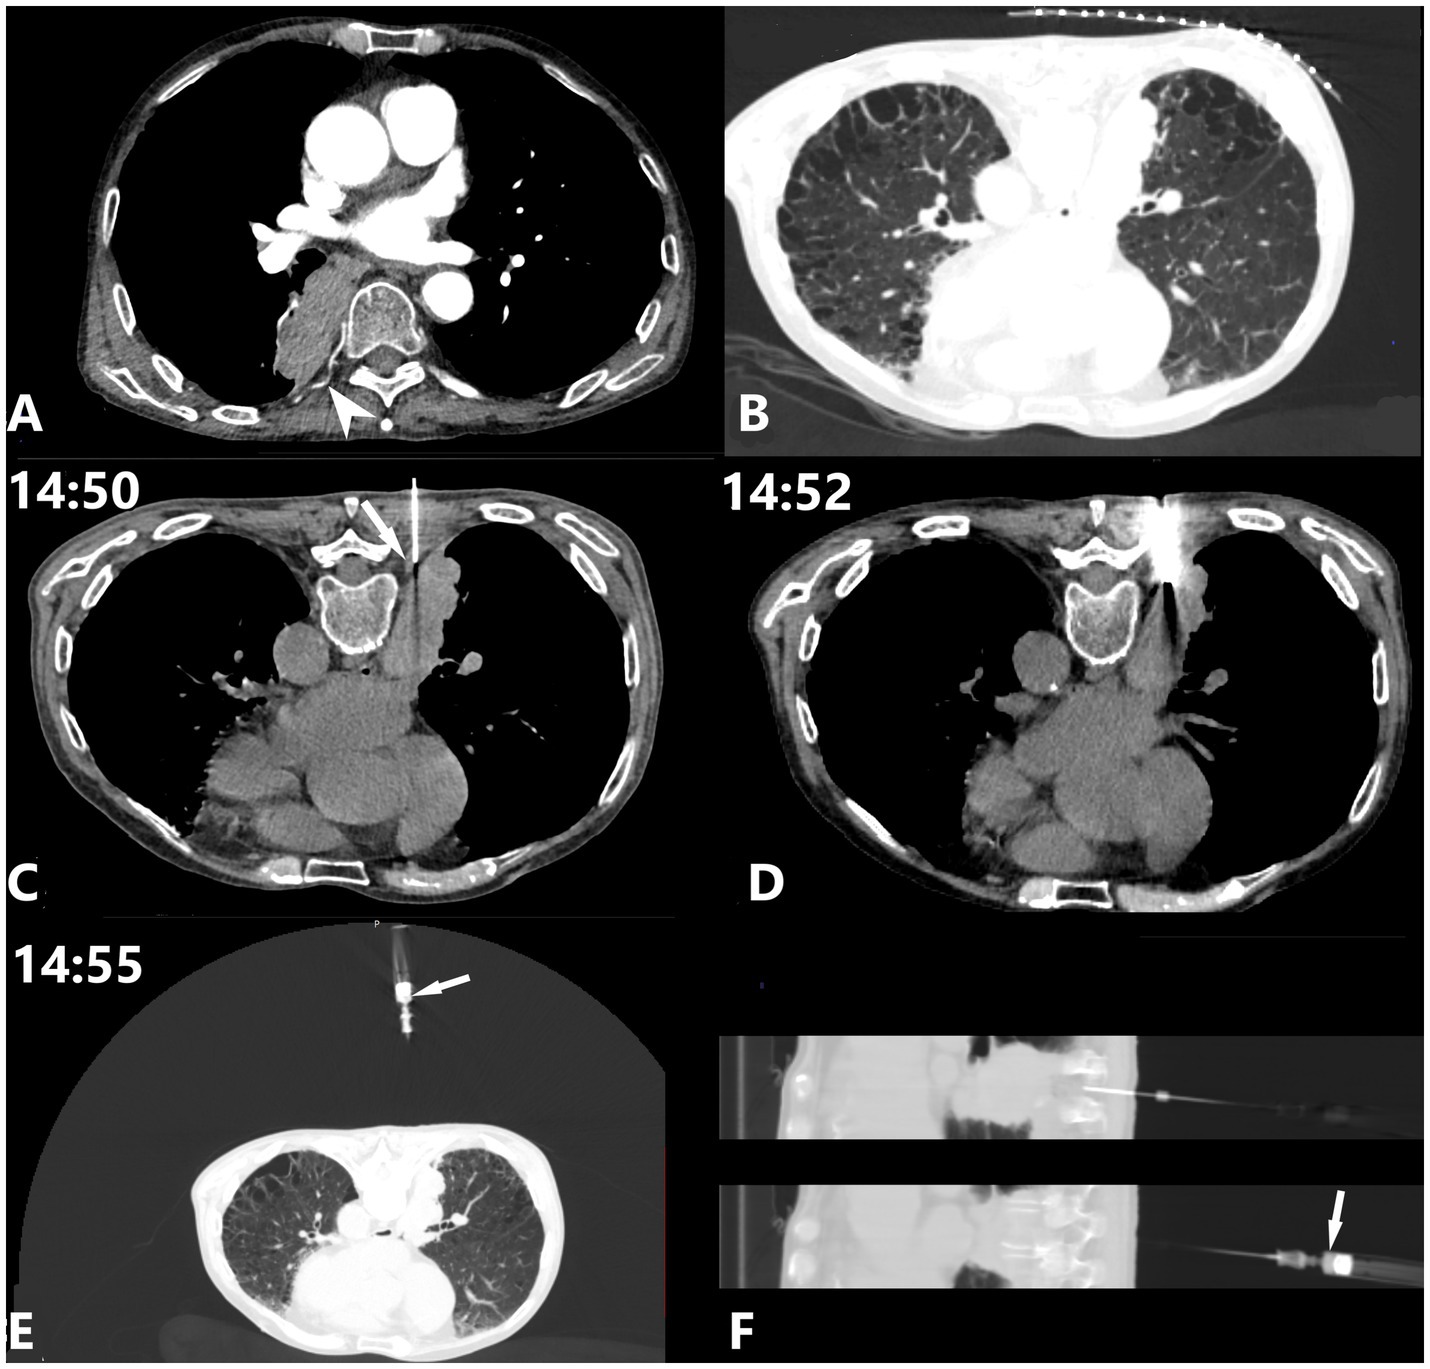

Intercostal artery (ICA) injury during CT-guided percutaneous transthoracic needle biopsy (PTNB) is a rare but potentially severe complication. This case report describes a cautious approach for detecting and managing suspected ICA injury using a coaxial needle system. During PTNB in a 71-year-old male with lung cancer, ICA injury was detected through blood aspiration during needle withdrawal. Management involved immediate cessation of withdrawal, slight needle advancement for mechanical hemostasis, and serial monitoring, achieving hemostasis without requiring additional invasive interventions. Literature review of cases from 2018 to 2024 revealed that current management approaches vary based on severity, with a 30% mortality rate among reported cases. Most ICA injuries are detected post-procedurally rather than intraoperatively. Traditional interventions range from conservative treatment to transcatheter arterial embolization (TAE) or thoracotomy. This approach suggests a potential stepwise method for managing suspected ICA injury that might reduce complications and minimize the need for invasive interventions. As a single case report representing hypothesis-generating evidence, this observation requires further validation through collaborative experience from other operators when similar circumstances arise. The case demonstrates an exploratory approach for managing ICA injury during PTNB, particularly relevant in resource-limited settings where interventional radiology services may not be immediately available.